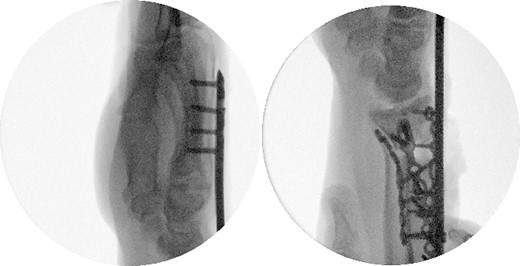

Two weeks following the procedure, the patient returned to the clinic for a follow-up visit. The wrist was swollen and ROM was limited. Hand motor functions and neurovascular exam were fully intact. Radiographs taken in clinic showed intact hardware with healing fracture. At 2 months follow-up, radiographs showed intact hardware with interval bone bridging across fracture sites. Radiographic parameters including articular alignment, radial height, radial inclination, and volar tilt were in acceptable ranges (Fig. 5). The patient reported no concerns or complications. A computed tomography (CT) scan was obtained at 10 weeks after the procedure and confirmed adequate bony healing and alignment without failure (Fig. 6). The dorsal spanning plate was eventually removed 1 month later and 4 months since the initial operation (Fig. 7).

CT assessment at 10 weeks postprocedure with coronal and sagittal cuts.